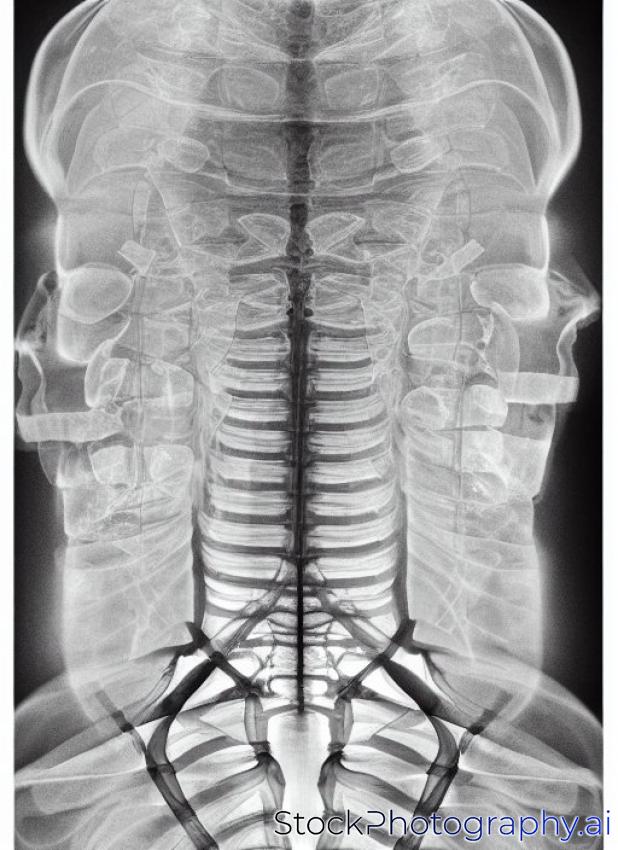

X-ray of head / Many others X-ray images in my portfolio

anatomy area background bones care check clinic dark examination examine eye face head health healthcare hospital human image injury inside joint l link medical neck picture radiological ray report roentgen segment skeleton skull spinal spine spinebone trauma traumatology upper urgent vertebra vertebral x x-ray-

- Category Healthcare/Medical